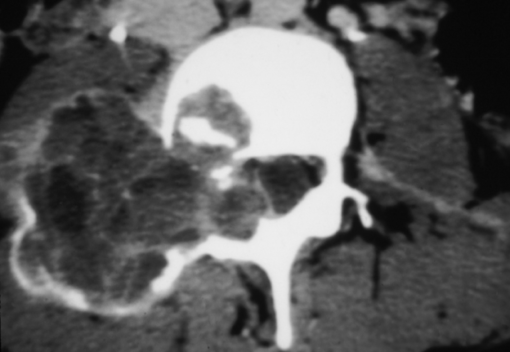

Degenerative joint disease in the spine lies at the crossroads of musculoskeletal and neuroimaging.

MRI Mastery Series: Degenerative Joint Disease (DJD) 2020 In this series, Dr. Dave Yousem provides his perspective on degenerative joint disease (DJD) as a practicing neuroradiologist. He reviews the current nomenclature for disc pathology, some of the common locations for disc herniation and the surgical implications/outcomes of the varying degrees of disc injury. The Degenerative Joint Disease Mastery series provides more than a dozen case reviews of the diagnoses surrounding DJD.

- Sequestrated discs

- Herniated discs

- Disc protrusions

- Annular fissures

- Disc Herniation vs Disc Bulge

- Disc Herniation vs Disc Extrusion

- Sequestrated Disk

- Disc Protrusion

- Disc Extrusion

- L Foraal Disc Herniation

- Cervical Disc Extrusion

- Synovial Cyst

- Synovial Cyst Posteriorly Projecting